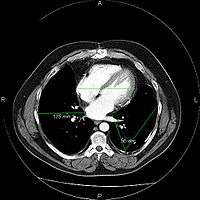

A picture archiving and communication system (PACS) is a medical imaging technology which provides economical storage and convenient access to images from multiple modalities (source machine types).[1] Electronic images and reports are transmitted digitally via PACS; this eliminates the need to manually file, retrieve, or transport film jackets. The universal format for PACS image storage and transfer is DICOM (Digital Imaging and Communications in Medicine). Non-image data, such as scanned documents, may be incorporated using consumer industry standard formats like PDF (Portable Document Format), once encapsulated in DICOM. A PACS consists of four major components: The imaging modalities such as X-ray plain film (PF), computed tomography (CT) and magnetic resonance imaging (MRI), a secured network for the transmission of patient information, workstations for interpreting and reviewing images, and archives for the storage and retrieval of images and reports. Combined with available and emerging web technology, PACS has the ability to deliver timely and efficient access to images, interpretations, and related data. PACS breaks down the physical and time barriers associated with traditional film-based image retrieval, distribution, and display.

Most PACSs handle images from various medical imaging instruments, including ultrasound (US), magnetic resonance (MR), Nuclear Medicine imaging, positron emission tomography (PET), computed tomography (CT), endoscopy (ES), mammograms (MG), digital radiography (DR), computed radiography (CR), Histopathology, ophthalmology, etc. Additional types of image formats are always being added. Clinical areas beyond radiology; cardiology, oncology, gastroenterology, and even the laboratory are creating medical images that can be incorporated into PACS. (see DICOM Application areas).

Typically a PACS consists of a multitude of devices. The first step in typical PACS systems is the modality. Modalities are typically computed tomography (CT), ultrasound, nuclear medicine, positron emission tomography (PET), and magnetic resonance imaging (MRI). Depending on the facility's workflow most modalities send to a quality assurance (QA) workstation or sometimes called a PACS gateway. The QA workstation is a checkpoint to make sure patient demographics are correct as well as other important attributes of a study. If the study information is correct the images are passed to the archive for storage. The central storage device (archive) stores images and in some cases reports, measurements and other information that resides with the images. The next step in the PACS workflow is the reading workstations. The reading workstation is where the radiologist reviews the patient's study and formulates their diagnosis. Normally tied to the reading workstation is a reporting package that assists the radiologist with dictating the final report. Reporting software is optional and there are various ways in which doctors prefer to dictate their report. Ancillary to the workflow mentioned, there is normally CD/DVD authoring software used to burn patient studies for distribution to patients or referring physicians. The diagram above shows a typical workflow in most imaging centers and hospitals. Note that this section does not cover integration to a Radiology Information System, Hospital Information System and other such front-end system that relates to the PACS workflow.